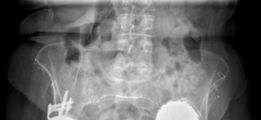

This image likely depicts a follow-up radiograph, showing continued good position of the components and signs of early bone graft incorporation, or potentially a different projection to confirm cage integrity.